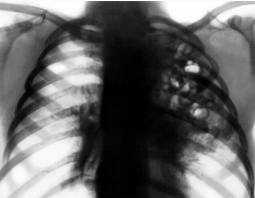

Заболевание начинается с головной боли, слабости, снижения аппетита, возможно развитие диареи. Быстро повышается температура до 39-40 °С, нарастают признаки тяжёлой интоксикации. Больные жалуются на озноб, головную боль, боли в мышцах и суставах, выраженную потливость. Развиваются общая слабость, адинамия. Появляются признаки токсического поражения ЦНС: эмоциональная лабильность, заторможенность, галлюцинации, потеря сознания и бред. Иногда наблюдают атаксию, дизартрию, нистагм, паралич глазодвигательных мышц. К середине недели возникает кашель, сначала сухой, затем со скудной слизисто-гнойной, а у части больных с кровянистой мокротой. Развиваются одышка, сильные боли в груди, особенно при сопутствующем фибринозном плеврите. В лёгких выявляют большое количество сухих и влажных мелкопузырчатых хрипов.

ДИАГНОСТИКА

При постановке диагноза учитывается эпидемиологическая обстановка, жалобы больного, клиническая картина заболевания, данные лабораторного и инструментального исследований. Проводится исследование крови, мочи, ЭКГ, рентген легких, кровь на серологию (обнаружение антител к легионеллам), иммуноферментный анализ, реакция иммунофлюоресценции, УЗИ брюшной полости.

Медицинские процедуры, проводимые при заболевании болезнь легионеров: Биохимический анализ крови, Клинический анализ крови, Анализ мочи, ЭКГ, Рентген, Реакция иммунофлюоресценции (РИФ), Иммуноферментный анализ, Серология, УЗИ брюшной полости